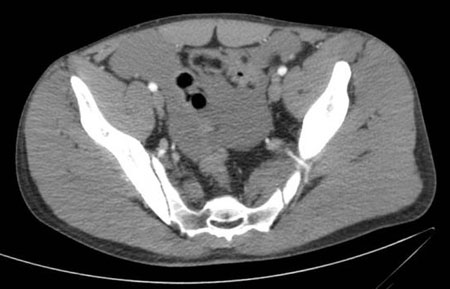

Exploración por TC que muestra líquido intraperitoneal

Colección del MetroHealth Medical Center